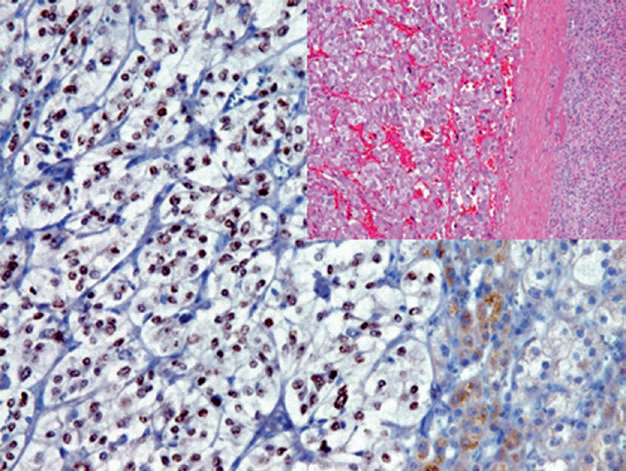

DAX-1也是孤儿核受体家族成员之一,这一核受体蛋白的功能是抑制前述SF-1的功能、从而抑制肾上腺皮质中类固醇激素的产生。此外,DAX-1在下丘脑-垂体-肾上腺-性腺轴(hypothalamic-pituitary-adrenal-gonadal axis)发育、骨母细胞分化中具有持续作用。DAX-1的表达仅限于产类固醇激素的细胞,如肾上腺皮质、垂体、下丘脑、睾丸、卵巢等处的相关细胞。与SF-1相似,DAX-1是肾上腺皮质肿瘤及卵巢、睾丸、乳腺中某些肿瘤的标记。需要注意的是,由于Ewing肉瘤相关的遗传学异常(EWS/Fli-1易位)促进了DAX-1的表达,因此该指标也可作为Ewing肉瘤的特异性指标。前述性索肿瘤章节对该指标已有描述。正常情况下,inhibin表达于性腺及肾上腺,不过肾上腺中表达最强的部位是肾上腺皮质的束状带、网状带,肾上腺髓质并不表达。因此除了前述睾丸和卵巢的性索肿瘤外,inhibin也是良性及恶性肾上腺皮质肿瘤的重要标记。

图2. 肾上腺皮质腺瘤,inhibin在胞质阳性。